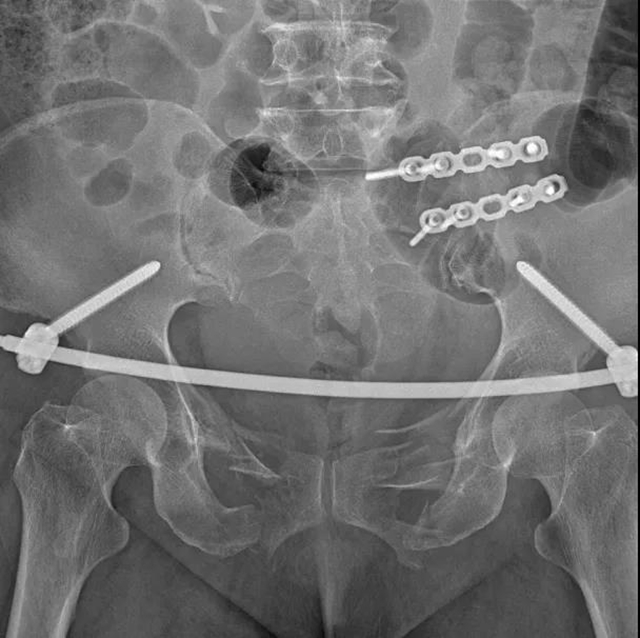

INFIX微创手术,给力

合江县中医医院骨伤科接诊后,根据两位阿姨的情况,主任陈宝华、副主任陈文辉及医生蒋伟采用先进技术——经皮骨盆前环内支架固定技术(INFIX)以及后环切开复位接骨板内固定技术,成功为两位阿姨完成了骨折复位及内固定手术。手术借助迷你切口固定骨折,术中前环两处切口均不到2厘米,出血约15毫升。术后,两位阿姨恢复良好。

而经皮骨盆前环内支架固定技术(INFIX),取双侧髂前下棘皮肤小切口植入椎弓根螺钉,两螺钉间建立皮下隧道,连接杆经过皮下隧道连接椎弓根螺钉后,通过间接复位技术使骨盆骨折复位并固定,具有时间短、创伤小、出血少、恢复快等优势,不破坏骨盆周围的韧带及软组织,结合了内固定和外固定的优点,有效避免了术后深部感染及使用外固定的手术并发症,是治疗骨盆前环损伤的一种最新的微创内固定方法。

迷你切口固定骨折,即达到治疗效果,又不失美观,可以使患者早期功能锻炼,并借助支具下地站立,最大程度上降低因伤致残机率,对患者的日常生活影响小,有效减轻了患者的精神和经济负担。